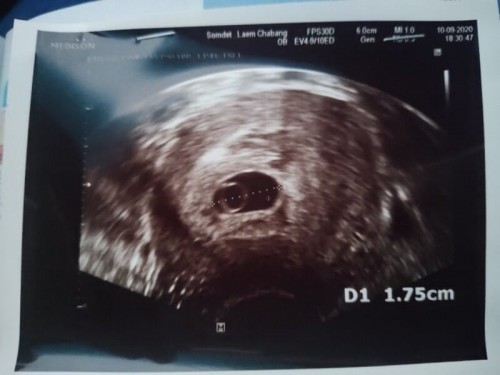

อยากสอบถามแม่ๆบ้านอื่นคะ อัลตราซาวด์เจอลูกๆกันตอนกี่ week. คะ ตอนนี้แม่ได้ 8 week ไปฝากครรภ์แต่อัลตราซาวด์ไม่เจอค่ะ คุณพ่อจิตตกมาก 😔

บ้านนี้ฝากครรภ์ครั่งแรก6weekก็เจอถุงตั่งครรภ์แล้วค่ะ